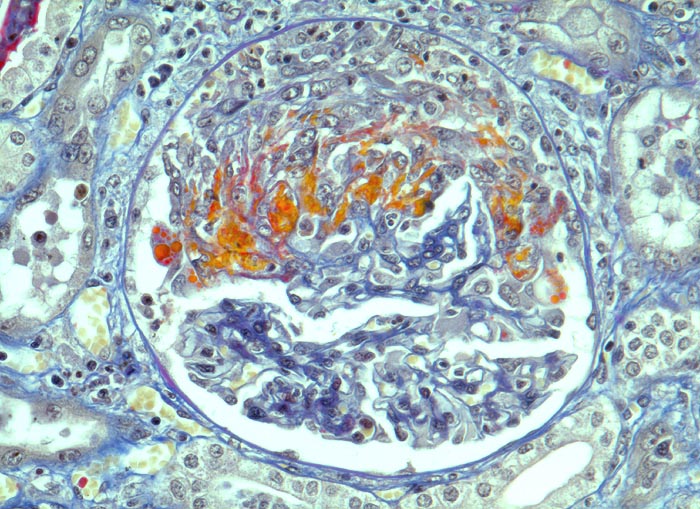

extrakapilläre Glomerulonephritis bei Morbus Wegener

Frische segmentale Schlingennekrosen mit exsudiertem Fibrin und Protein (rot). Beginnende Proliferation von Kapselzellen. Dazwischen einzelne neutrophile Granulozyten.

Halbmondbildung: Sichelförmige Proliferation von Kapselepithelien als Antwort auf eine lokale Fibrinexsudation aus geschädigten/nekrotischen Glomeruluskapillaren.

Histologie

320